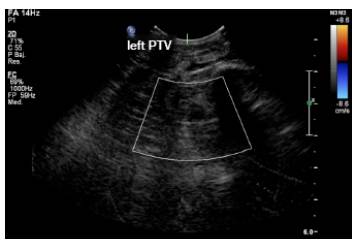

The Doppler ultrasound of the lower limb showed thrombosis of the external iliac and left common femoral veins (Figures 2 and 3). The chest x-ray, performed due to suspicion of septic pulmonary embolism, showed acinar nodule lesions (Figure 4). The CT scan showed pulmonary and subpleural nodules (Figure 5), and a D-dimer value of200-00 ng/dL was determined (reference <200). Consequently, it was confirmed that the patient had venous thromboembolism and septic pulmonary embolism. Echocardiogram and abdominal ultrasound were normal. The treatment with oxacillin was continued and the new blood cultures, taken after five days, were negative. The patient completed 42 days of antibiotic and anticoagulant treatment, and was discharged with satisfactory evolution.

Doppler ultrasound of the left lower limb: superficial femoral vein thrombosis with retrograde flow.

Figure 2: Doppler ultrasound of the left lower limb: superficial femoral vein thrombosis with retrograde flow.

LSFV: left superficial femoral vein; LSFA; left superficial femoral artery. Source: Document obtained during the study.